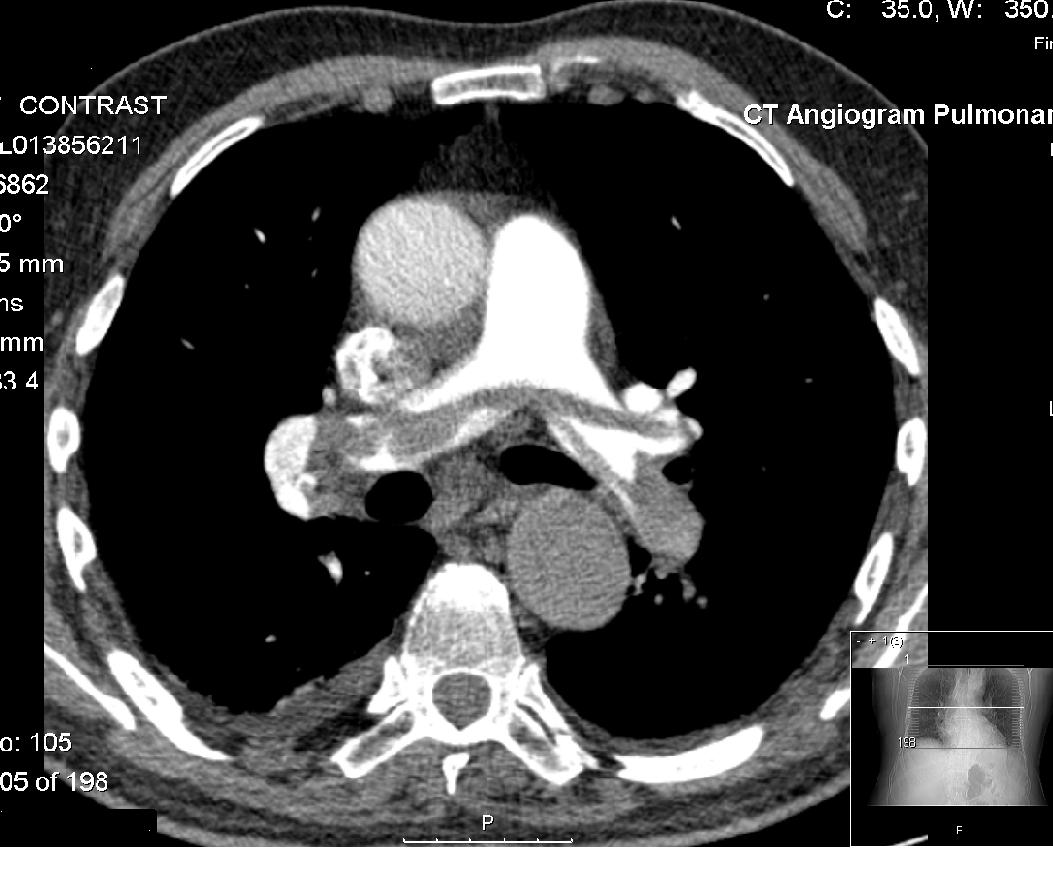

این نوشته ها در مورد خون و بیماری های لخته خون است. بیماری هایی مانند DVT ، آمبولی ریه ، تشکیل لخته خون در رگها و حفرات بدن ، سکته قلبی و مغزی.  بیماری هایی که بسیار شایع بوده و می توانند تهدید کننده سلامت و زندگی ما باشند.